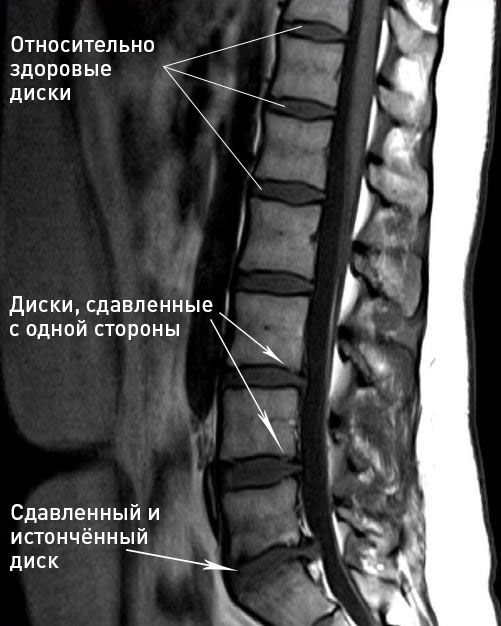

Остеохондроз — это повреждение хрящевой ткани позвоночника, поражение связочного аппарата с последующей деформацией костной ткани.

Главная причина — это отсутствие необходимых физических нагрузок на мышцы позвоночника или же неправильные, не сбалансированные нагрузки. Мышцы, не испытывающие нагрузок (или испытывающие дисбаланс нагрузок), слабеют и перестают поддерживать позвоночник в расправленном состоянии. В результате функция поддержки позвоночника «перекладывается» на межпозвонковые диски, которые к такой работе не приспособлены, поэтому они начинают стираться, истончаться и терять влагу.